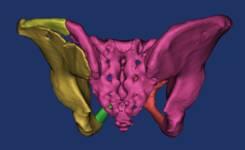

面对这一困境,市四医院骨一科手术团队联合数字医学中心,通过术前的骨盆模型三维重建,模拟复位,设计骶髂螺钉导航模板并3D打印,术中通过导板引导,成功置入骶髂螺钉,为患者进行手术治疗。

骨盆术前三维模型和模拟复位--正位后面观